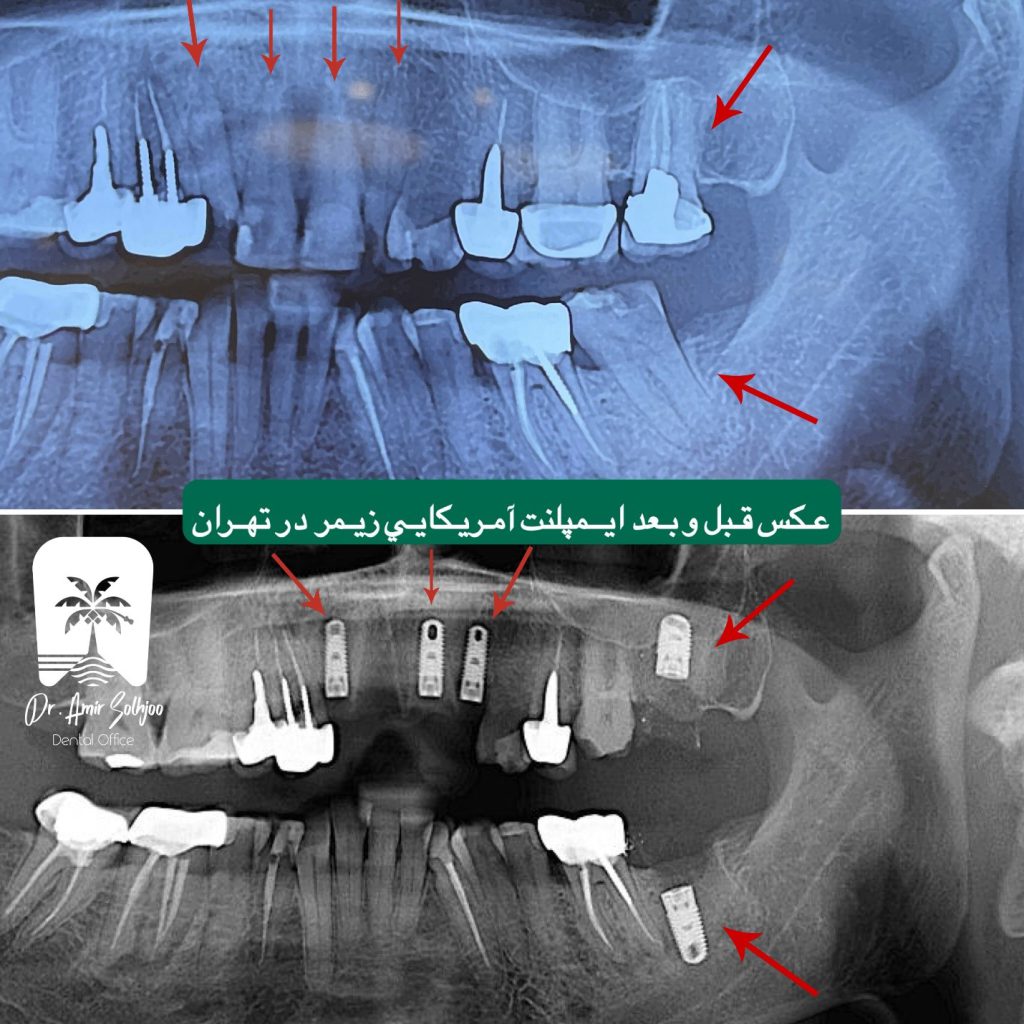

Zimmer(Zimmer)USATRP surface with microchannel technology for faster bone repair and stabilization (osteointegration), optimal design for bone preservation Aroundpeople who are looking for best quality and durability and have good bone conditions or need reconstruction.

Zimmer implant (American) + veneer58 to 68price for a quality complete unit Excellent